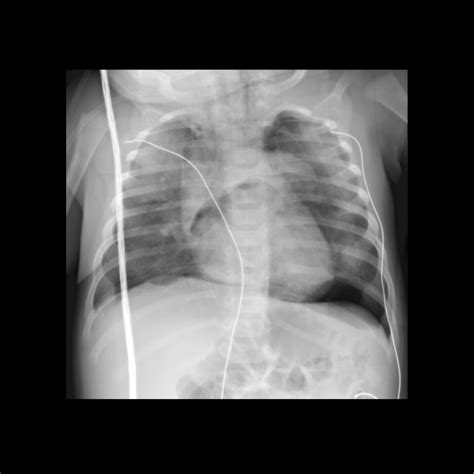

• Confirm Placement: Use a stethoscope to auscultate the epigastric area while injecting air through the tube. Listen for a gurgling sound, which indicates the tube is in the stomach. Alternatively, use a pH indicator strip to check the pH of the aspirate, which should be acidic (pH < 5.5) if the tube is in the stomach.

• Radiographic Guidance: Fluoroscopy or X-ray can be used to confirm the placement of the NG tube, especially in complex cases.

• ng tube placement xray

• ng tube placement xr